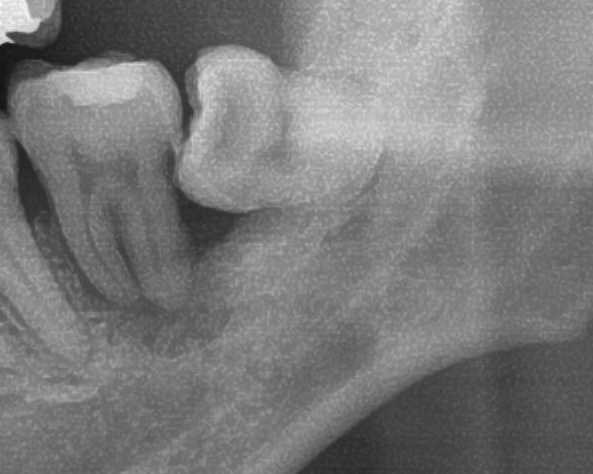

次にパノラマ写真を撮影してみると、左下の親知らずは手前の歯を押すように斜めに生えているのが確認できました。